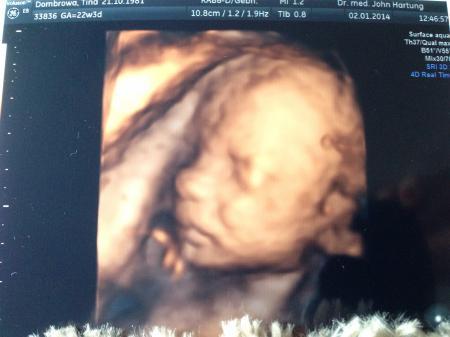

Noch nen Bildchen vom Mäuschen :-))))

Hallo zusammen, Ersteinmal ein gesundes neues Jahr wünsche ich euch allen. Ich ahne mich lange nicht gemeldet, aber immer fleißig mitgelesen. Am Donnerstag hatten wir Feindiagnostik und es war so schön das Baby zusehen und alles genaue zu erfahren. Der Magen war bei der letzte VU nicht darstellbar, jetzt konnten wir ihn super erkennen. Alles ist super und ich total erleichtert. Auch das Hämatom scheint sich komplett resorbiert zu haben, es war nirgends zufrieden. Ein eindeutiges Outing gab es auch wir bekommen eine kleine Püppi - ich bin sehr glücklich und erleichtert, die kleine Maus ist 27 cm groß und knapp 460gr schwer. Die Zeit rennt - das erste Märzbaby ist schon da und ehe man sich versieht ist der Mai bald ran. Hab mir heut meinen Traumkinderwagen bestellt, da er eine lange Lieferzeit hat wollte ich das schon mal erledigt haben es ist ein Hesba nach meinen wünschen. Schönes Woen euch allen glg luluuu